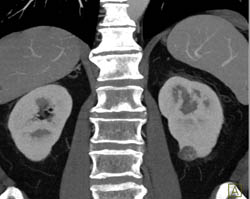

1 Cm Renal Cell Carcinoma